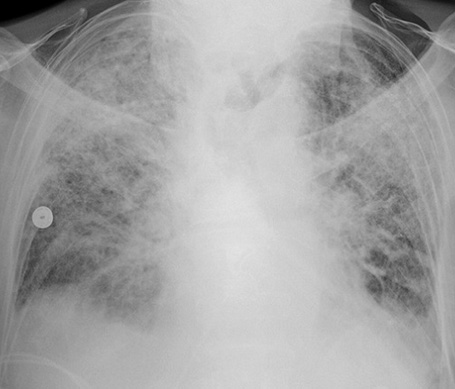

誘發(fā)急性呼吸窘迫綜合征的原因有哪些?在日常生活中有效的了解急性呼吸窘迫綜合征產(chǎn)生的原因,可以幫助我們更好的預(yù)防該疾病的產(chǎn)生,那么下面我們就來(lái)給大家介紹一下,一起來(lái)看看吧!

(一)肺水腫的產(chǎn)生 各種致病因素使肺血流灌注不足,直接損害肺泡、毛細(xì)血管上皮,引起肺泡毛細(xì)血管膜的通透性增加。血循環(huán)中的粒細(xì)胞、血小板及組織巨噬細(xì)胞釋放的各種炎癥介質(zhì)將加重上述損害。液體及蛋白質(zhì)等漏出血管外,導(dǎo)致肺水腫形成,影響通氣/灌注比率,導(dǎo)致低氧血癥。

(三)肺表面活性物質(zhì)減少 肺表面活性物質(zhì)襯附在肺泡表面.具有降低肺泡表面張力,瞅肺泡順應(yīng)性,穩(wěn)定肺泡內(nèi)壓,防止肺毛細(xì)血管內(nèi)液體滲入肺泡內(nèi)的功能。它由廈型肺泡上皮細(xì)胞的線粒體合成及分泌的,其主要成分為二棕憫酮亞磷脂,大約18—24小時(shí)更新一次。 急性呼吸窘迫綜合征發(fā)病時(shí),由于上述肺小血管痙攣及肺微小血管栓塞所致的肺血流減少,影響h型肺泡上皮細(xì)胞代謝,磷脂合成發(fā)生障礙;或由于水腫液、脂肪酸、氧個(gè)毒等因素直接破壞作用,使肺表面活性物質(zhì)減少,表面張力增高,肺泡縮小、陷閉,形成肺不張,同時(shí)肺毛細(xì)血管內(nèi)液體滲入肺間質(zhì)及肺泡。